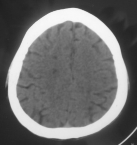

Hình 3.9. Nhồi máu não vùng vành tia – ranh giới giữa vùng tưới máu các nhánh nông và sâu của động mạch não giữa